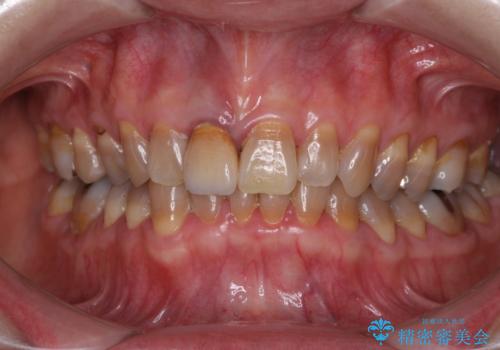

前歯が折れたついでに歯並びも改善 矯正治療と前歯のセラミック治療